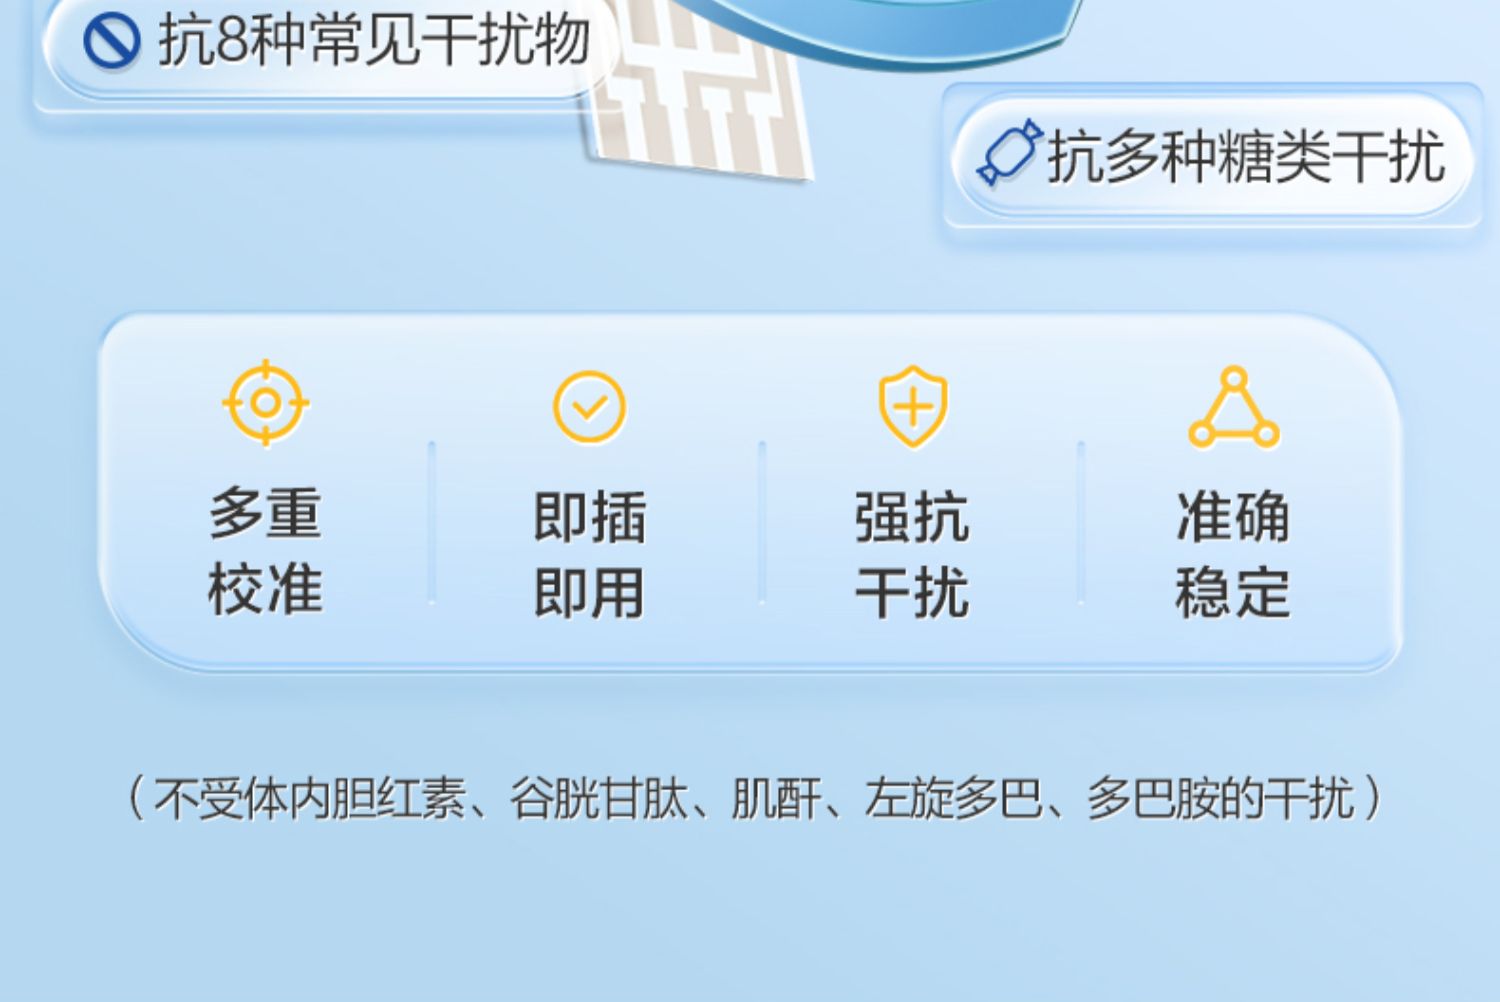

可孚新国标血糖测试仪家用测糖仪试纸官方旗舰店测血糖的仪器孕妇